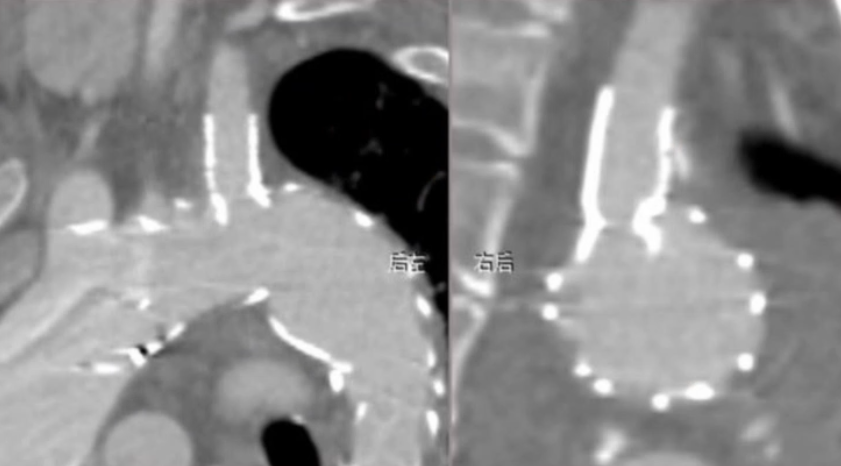

患者术后无神经系统定位体征,这意味着手术未对神经系统造成损伤,神经功能保持正常。术后五天复查CTA,可见假性动脉瘤瘤腔内已经完全血栓化,颈总动脉和锁骨下动脉分支血流通畅。出院前复查,LCCA与LSA分支形态良好,血流通畅,无狭窄,主动脉支架封闭效果好,无内漏,治疗效果令人满意。患者身体恢复良好,手术达到了预期治疗目标。

术前CTA

术后5天CTA